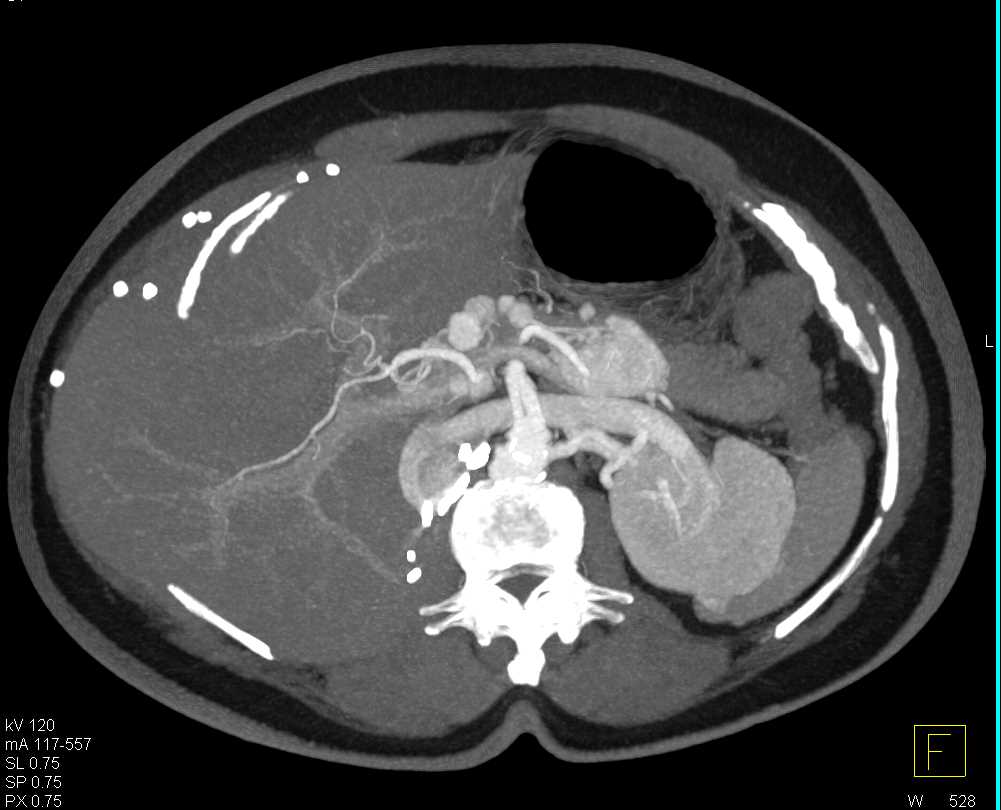

Clear Cell RCC with Metastases to the Pancreas